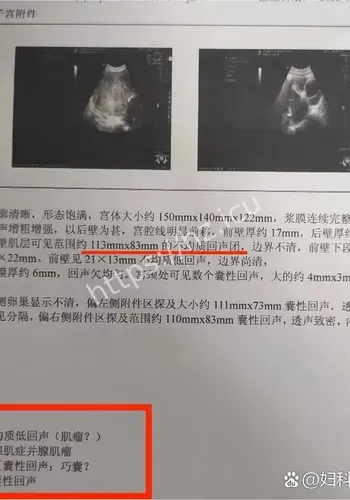

对观众来说,这类热点的影响,往往体现在它会不会改变自己对22厘米肌瘤致孕妇子的判断,或者会不会影响后续生活中的选择与讨论。检查揭示出一连串环环相扣的罕见致命危机:一个大小约为13.212.822.4厘米的巨大肌瘤,上缘顶至剑突,左右分别霸占整个腹腔,甚至超出超声探头的单一切面探测范围,并且提示血运丰富。因肌瘤推挤,子宫发生罕见的“箝闭”,即子宫体向后倾倒、死死卡在直肠窝内,宫底位置低于宫颈外口,整个子宫呈“倒置”状态。